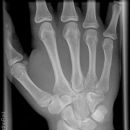

Hand / Handgelenk